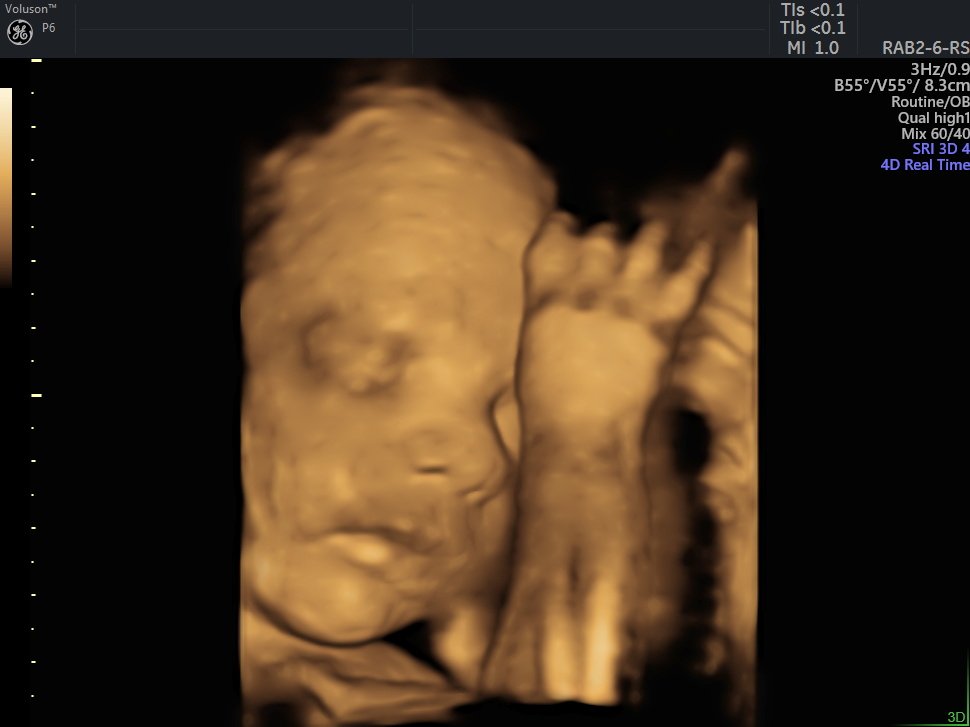

4 D Ultrasonografi

4 Boyutlu (Renkli) Ultrason ve Doppler Ultrasonografi